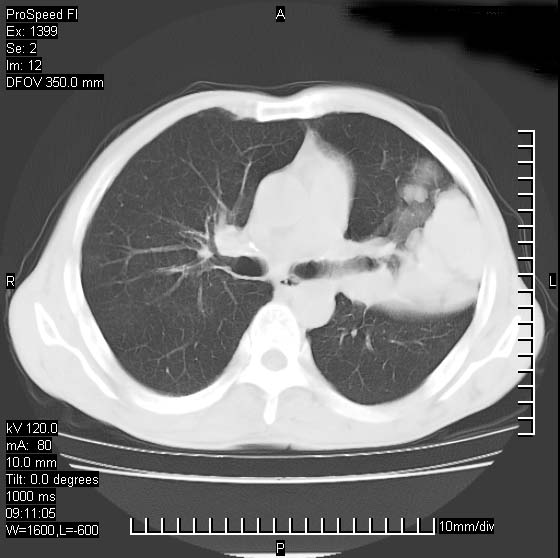

以下是引用rgsyyf在2007-1-19 11:05:00的发言:[br]左肺上叶见形态不规则巨大软组织肿块影,边缘呈分叶征,纵隔内隆突下见肿大淋巴结,右肺内另见一不规则结节影 .考虑:左肺周围性肺癌伴纵隔即右肺内转移.